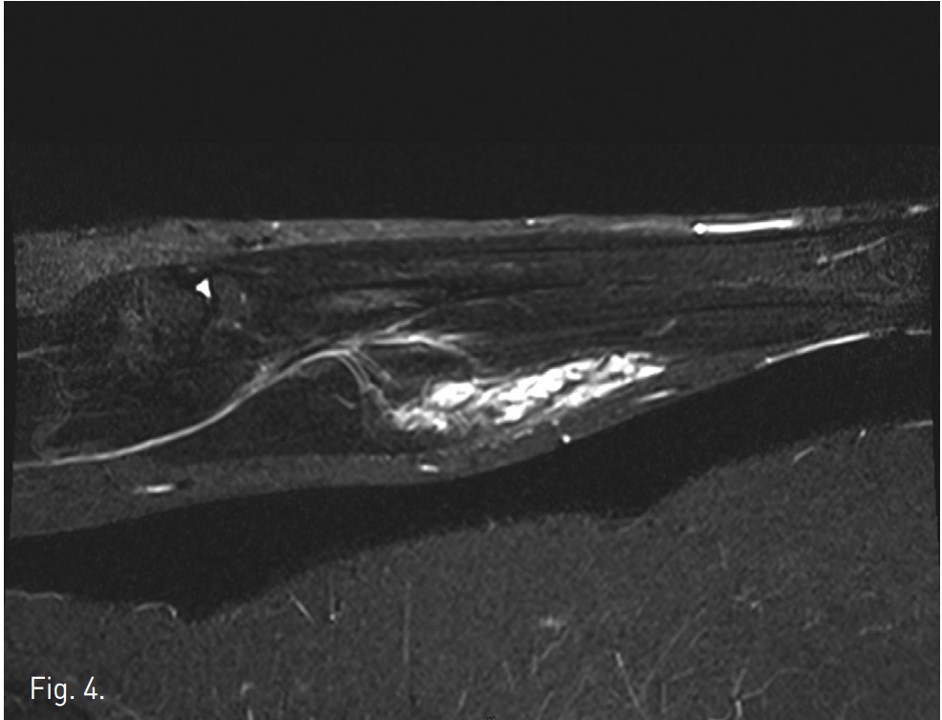

Venography demonstrates dilated, tortuous veins along the medial aspect of the proximal forearm draining into normal veins (Fig. 1). Negative digital subtraction angiography shows filling-defects from displaced contrast material in the vascular malformation during sodium tetradecyl sulfate foam injection (Fig. 2). A native image of the forearm demonstrates stasis of contrast material within the venous malformation after foam sclerotherapy (Fig. 3). T2 STIR imaging shows a 10.3 x 2.5 x 2.3 cm high signal intensity mass centered within the flexor digitorum superficialis consistent with slow-flow vascular malformation. The high signal represents the extent of the vascular malformation as well as post-treatment edema or inflammation (Fig. 4). Post-contra st T1 imaging with fat suppression demonstrates heterogeneous enhancement of the mass with notable areas of low signal representing the areas of thrombosis/sclerosis. The residual irregular enhancement represents postprocedural inflammation. Of note, there are no enhancing serpiginous structures (Fig. 5).

Fig. 4.

Fig. 4. T2 STIR imaging shows a 10.3x2.5x2.3 cm high signal intensity mass centered within the flexor digitorum superficialis consistent with slow-flow vascular malformation. The high signal represents the extent of the vascular malformation as well as post-treatment edema or inflammation.